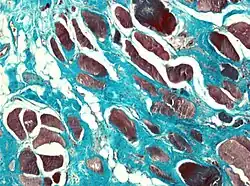

Muscle biopsies are also a useful tool to diagnose camptocormia. Muscle biopsies found to have variable muscle fiber sizes and even endomysial fibrosis may be markers of bent spine syndrome. In addition, disorganized internal architecture and little necrosis or regeneration is a marker of camptocormia.